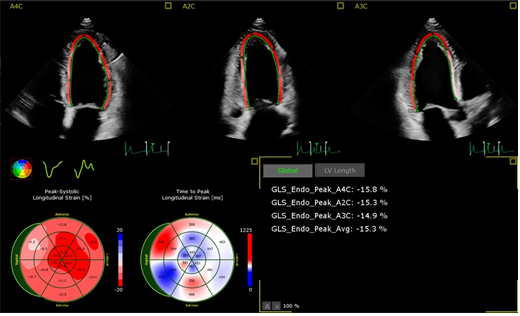

- Die zweite neue Methode ist das SpeckleTracking/Strain/Strain-Rate zur Vermessung der Verformung des Myokardiums (Strain, Strain-Rate über die Zeit). Die Beurteilung der Verformung (Dickenzunahme und – Abnahme) des Herzmuskels erfolgt segmental, ein negativer Kurvenverlauf ist wünschenswert. Aus der Kammeranalyse ergeben sich auch die enddiastolischen- und endsystolischen Volumina (EDVI/ESVI) und die Ejektionsfraktion EF nach der Scheibchenmethode Simpson in Prozent, letztere orientiert sich an humanvalidierten Werten > 40%.